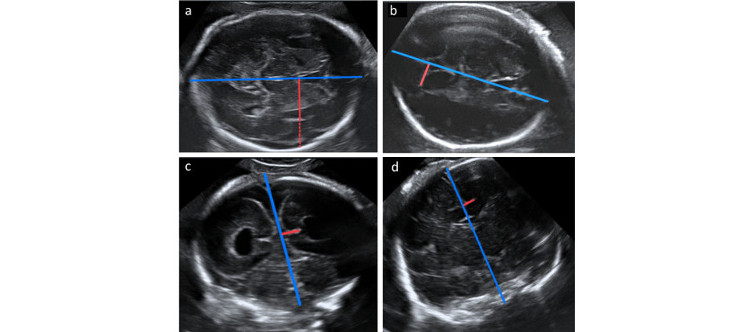

• CIBERCV

Identifican con precisión la fibrosis cardiaca mediante técnicas de imagen

12/04/2018